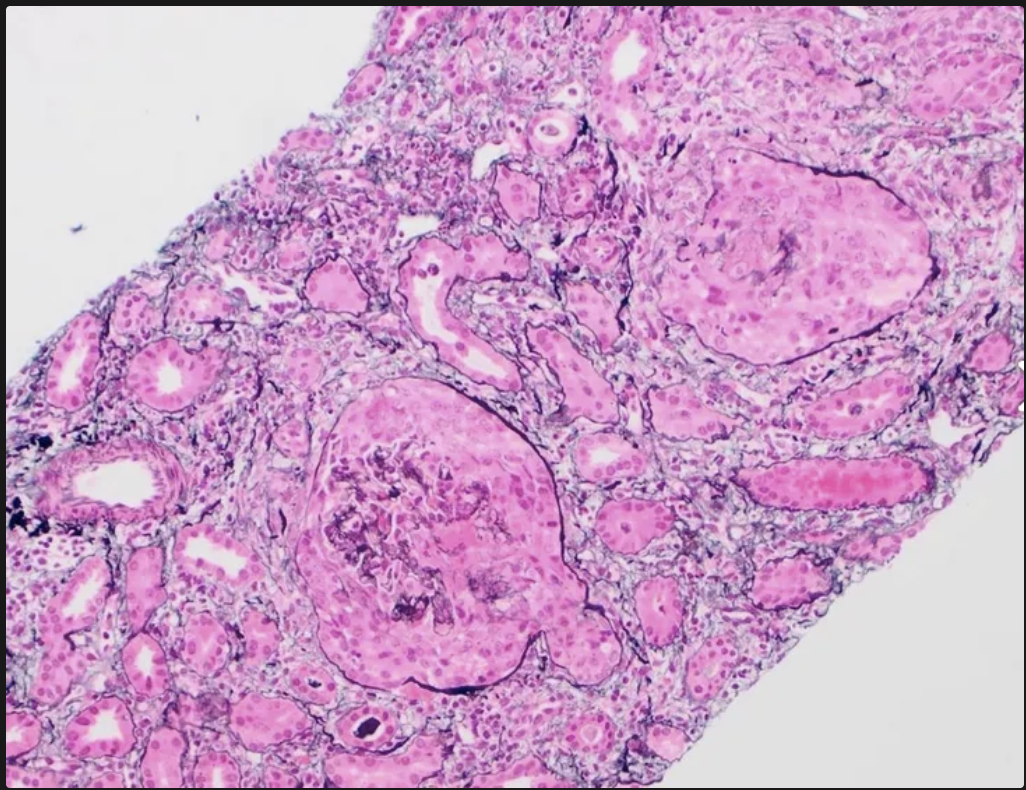

Microscopía óptica de la enfermedad de Berger

Glomérulos normales o con ensanchamiento mesangial

Presencia de leucocitos en capilares glomerulares

Lesiones visibles: la curación lleva a esclerosis focal y segmentaria, necrosis con formación de estructuras semilunares

En la inmunofluorescencia de la enfermedad de berger se pueden ver depósitos de ______, puede haber ___ y ____ y cantidades menores de IgG o IgM

IgA; C3; properdina